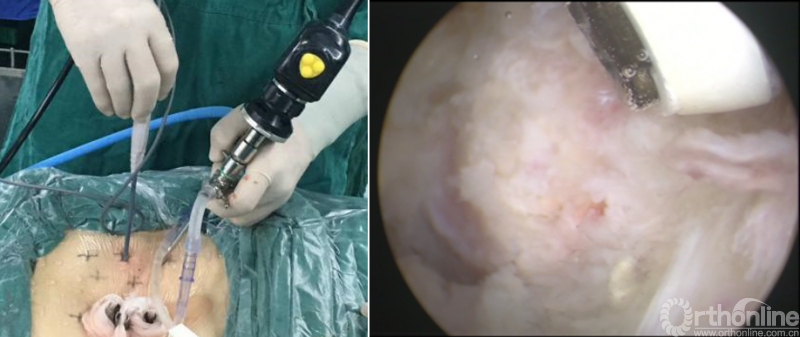

第二步“剥”:剥离器+射频剥离、止血、造腔,显露下关节突尖部;

第三步“凿”:凿除部分下关节突;

第四步“分”:分离上关节突及黄韧带;

第五步“咬”:咬除部分上关节突,显露椎间盘及神经根;

第六步“切”:切除椎间盘;

第七步“牵”:神经拉钩牵拉保护神经根;

第八步“铰”:铰刀置入处理上下终板(刮勺置入处理终板);

第九步“填”:椎间隙填塞植骨;

第十步“置”:置入融合器、经皮钉。